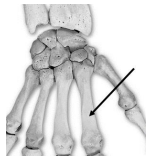

Considere a imagem a seguir:

No que tange aos conceitos de anatomia humana, os ossos assinalados na imagem são denominados: